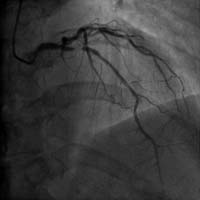

前降支近端嚴重狹窄 介入術后狹窄消失